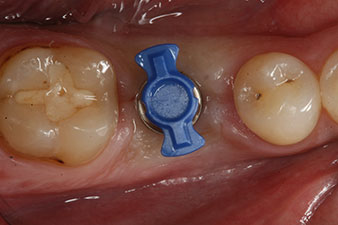

En outre, après avoir vissé une tige de mesure (SmartPeg) spécialement conçue pour l'implant, la valeur ISQ a été mesurée à l’aide de la sonde du module W&H Osstell ISQ.

Ce module est fourni en option avec l’Implantmed de W&H et est fixé au moteur d’implantologie (cf. Fig. 11). La valeur ISQ adimensionnelle mesurée immédiatement après l’insertion était de 64 dans l’axe oro-vestibulaire et de 68 dans l’axe mésio-distal (valeur maximale = 100).

Ces valeurs auraient pu indiquer une cicatrisation ouverte, voire une restauration immédiate. Étant donné le volume osseux crestal insuffisant au niveau de l’implant, une augmentation osseuse a été pratiquée localement à l’aide des fragments osseux recueillis lors de la préparation du lit implantaire, et des points de suture effectués pour éviter le contact de la salive.